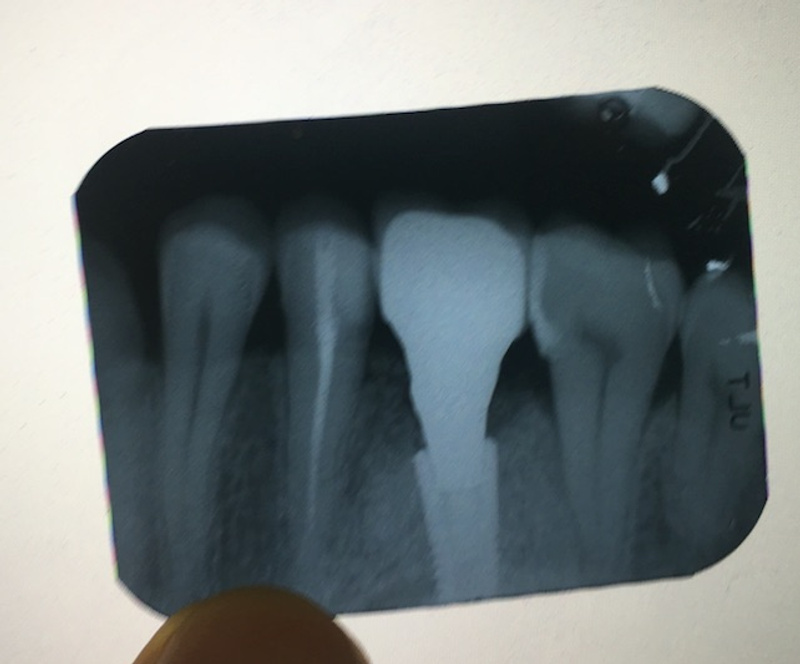

Помогите сориентироваться. Более года назад был установлен зубной имплант АстраТек в дополнению к импланту была использована искусственная кость ( не уверен за название, сильно не пинайте).

Так получилось, что коронка установить не смогли, она у меня на руках. Насколько я понял фактически ее установить еще можно. Не установили ее сразу потому что после 3-х месяцев имплант еще не до конца прижился и коронку не могли "вкрутить" используя полную силу и решили подождать еще немного но так уж получилось что в итоге коронка у меня на руках и второй раз не пробовали ставить. Сам имплант закрыли каким то специальным болтом. Это вводная. Вообще меня этот имплант особо не беспокоил но последнее время начинает изредко ныть и побаливать.

Фото коронки и рентгена прилагаю.